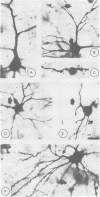

Neuropathological findings in a 38 year old patient with dementia of frontal lobe type and motor neuron disease included pyramidal tracts, myelin pallor and neuron loss, gliosis and chromatolysis in the hypoglossal nucleus, together with frontal atrophy, neuron loss, gliosis and spongiosis in the upper cortical layers of the frontal (and temporal) lobes. Most remaining pyramidal and non-pyramidal neurons (multipolar, bitufted and bipolar cells) in the upper layers (layers II and III) of the frontal cortex (area B) had reduced dendritic arbors, proximal dendritic varicosities and amputation of dendrites as revealed in optimally stained rapid Golgi sections. Pyramidal cells in these layers also showed depletion of dendritic spines. Neurons in the inner layers were preserved. Loss of receptive surfaces in neurons of the upper cortical layers in the frontal cortex are indicative of neuronal disconnection, and are "hidden" contributory morphological substrates for the development of dementia.